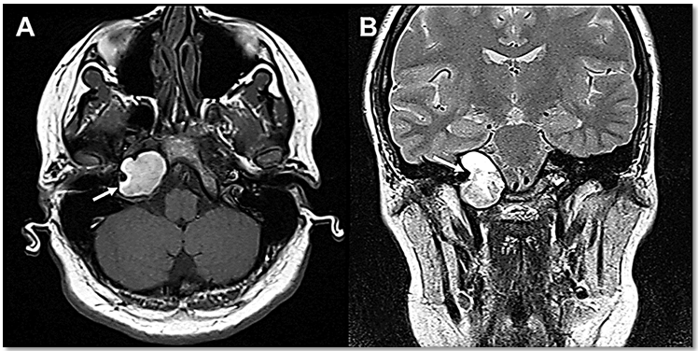

Homem, 50 anos, com quadro de perda auditiva neurossensorial à direita de grau

leve, é submetido a estudo de ressonância magnética sem contraste, onde foram observadas as

seguintes imagens:

Sobre o caso, assinale a alternativa correta.